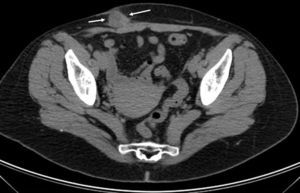

TC pélvica con contraste por vía intravenosa de la paciente de la figura 1. Lesión nodular (entre flechas) de densidad similar al tejido blando con realce periférico tras la administración del contraste por vía intravenosa, con zonas hipodensas en su interior, situada en el tejido subcutáneo bajo la cicatriz de la cesárea.

En el estudio de TC los endometriomas se muestran como masas bien definidas sólidas o mixtas, isodensas con respecto a la musculatura adyacente e incluso hiperdensas (en caso de hemorragia), que realzan heterogéneamente tras la administración del contraste intravenoso. La afectación inflamatoria anular se identifica como un aumento de la densidad de los planos grasos de alrededor2,8,10.